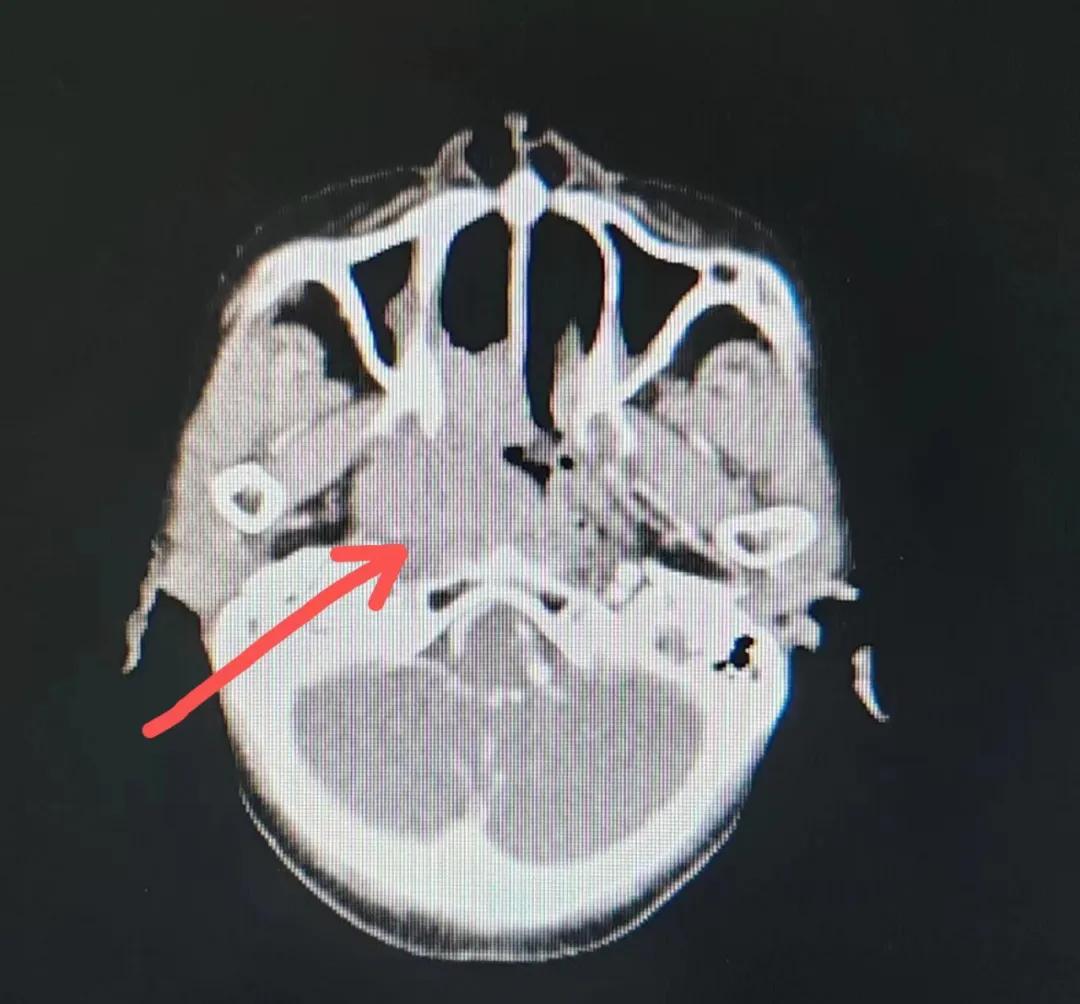

治療后

放療結(jié)束,除了放療處的皮膚輕微放射性皮炎外,基本沒(méi)有什么不良反應(yīng)。復(fù)查發(fā)現(xiàn),鼻腔淋巴瘤已不可見(jiàn),目前患者已康復(fù)出院。